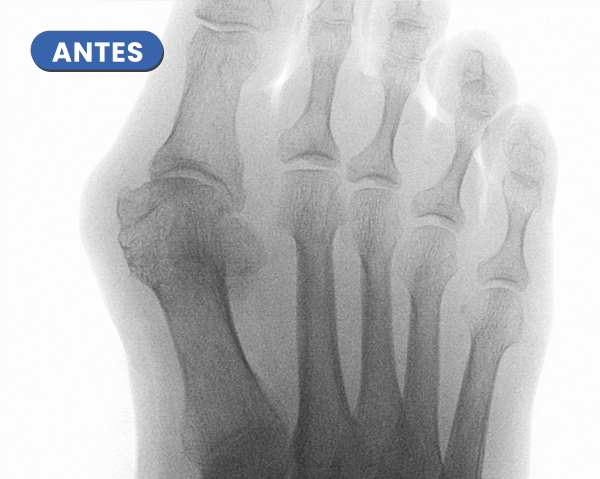

En la imagen cabe destacar la desaparición del juanete y del heloma o cayo sobre el cuarto dedo.

La corrección del Juanete nos permite modificar la desestructuración de los dedos menores segundo y tercero que este caso está en ráfaga y este último sobre el dedo vecino, cuarto dedo.

En este caso típico que el Juanete es la causa de una lesión dérmica, que en múltiples ocasiones tarda en curar por el compromiso o roce con el calzado.